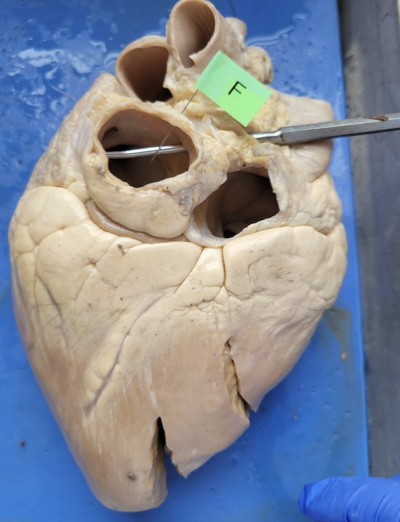

what is this

the left atrium

what is this

right ventricle

what is this

Aorta

what is this

the left ventricle

what is this

pulmonary artery

what is this

pulmonary vein